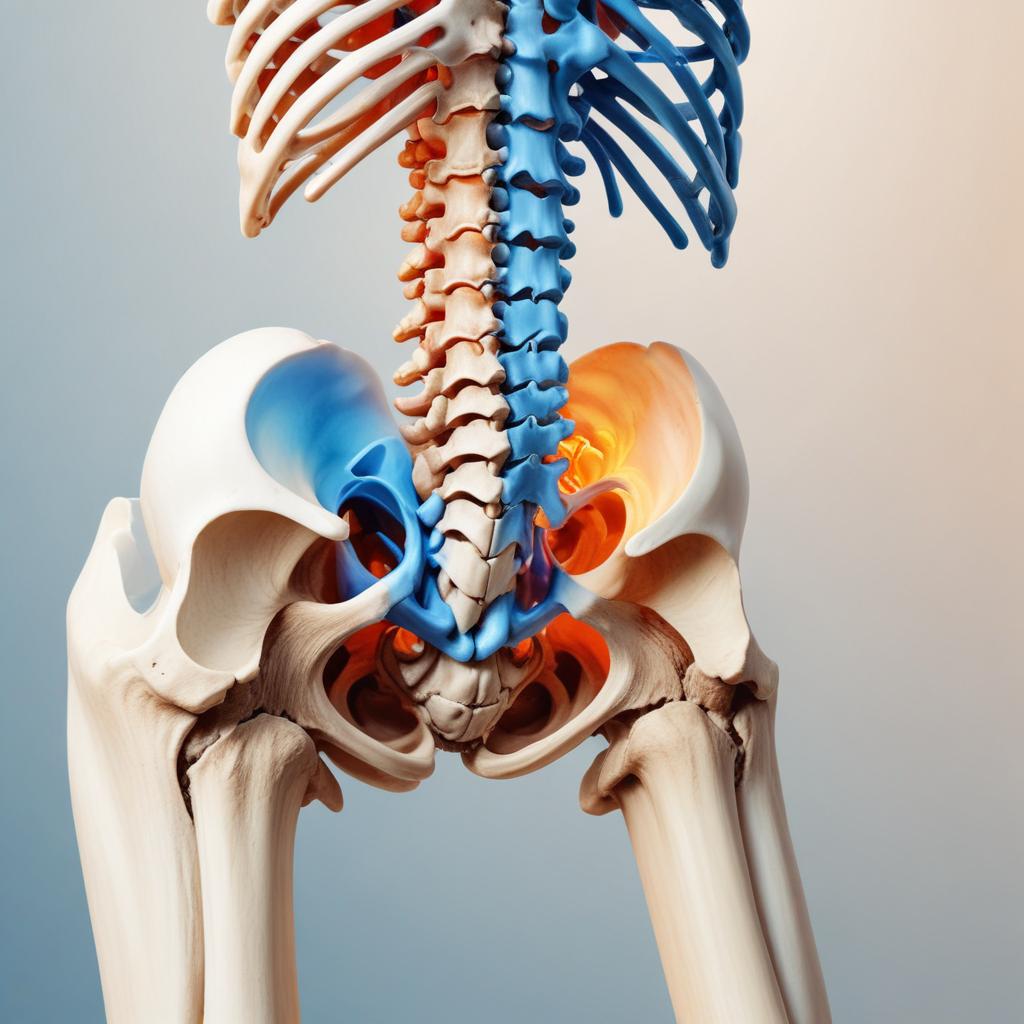

Боли в бёдрах — это частый симптом, который зачастую воспринимается исключительно как результат физических травм, воспалений или дегенеративных процессов. Однако основы психосоматики показывают, что такой дискомфорт может иметь и психологическую природу. Наше тело часто реагирует на эмоциональные переживания, переносит внутренние конфликты в физическую плоскость, что и проявляется, например, в виде болей.

Значение симптомов, возникающих в области бёдер, иногда связано с подсознательным ощущением неуверенности, страха перед будущим или ограниченности в движениях — как в буквальном, так и в переносном смысле. Психологические блоки и эмоциональные травмы могут накапливаться, вызывая напряжение мышц и сосудистые нарушения, которые и становятся причиной болей в этой зоне.

Область бёдер играет важную роль в поддержании устойчивости и мобильности тела, поэтому мышцы и суставы в этой зоне особенно чувствительны к изменениям в физиологии, вызванным стрессом. Психологический стресс провоцирует выброс гормонов, таких как адреналин и кортизол, которые влияют на мышечное напряжение и кровообращение. Это приводит к тому, что мышцы бёдер могут переходить в состояние постоянного тонуса или спазма, вызывая боли и дискомфорт.

Кроме того, суставы бёдер часто травмируются из-за неравномерного распределения нагрузки, которое может усиливаться из-за мышечного напряжения, вызванного психологическим стрессом. Также нарушение кровотока и лимфотока влияет на питание тканей и их восстановление, что усиливает болевые ощущения. Таким образом, боль в бёдрах – это не просто физический симптом, но и отражение внутреннего эмоционального и психологического состояния человека.